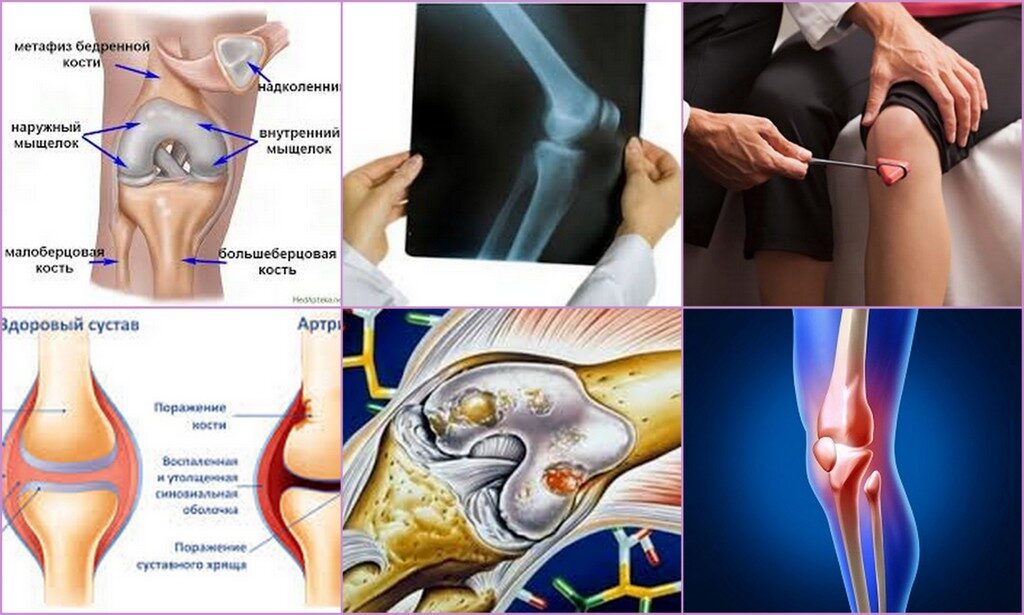

Анатомия коленного сустава: изучение анзерита и его влияния